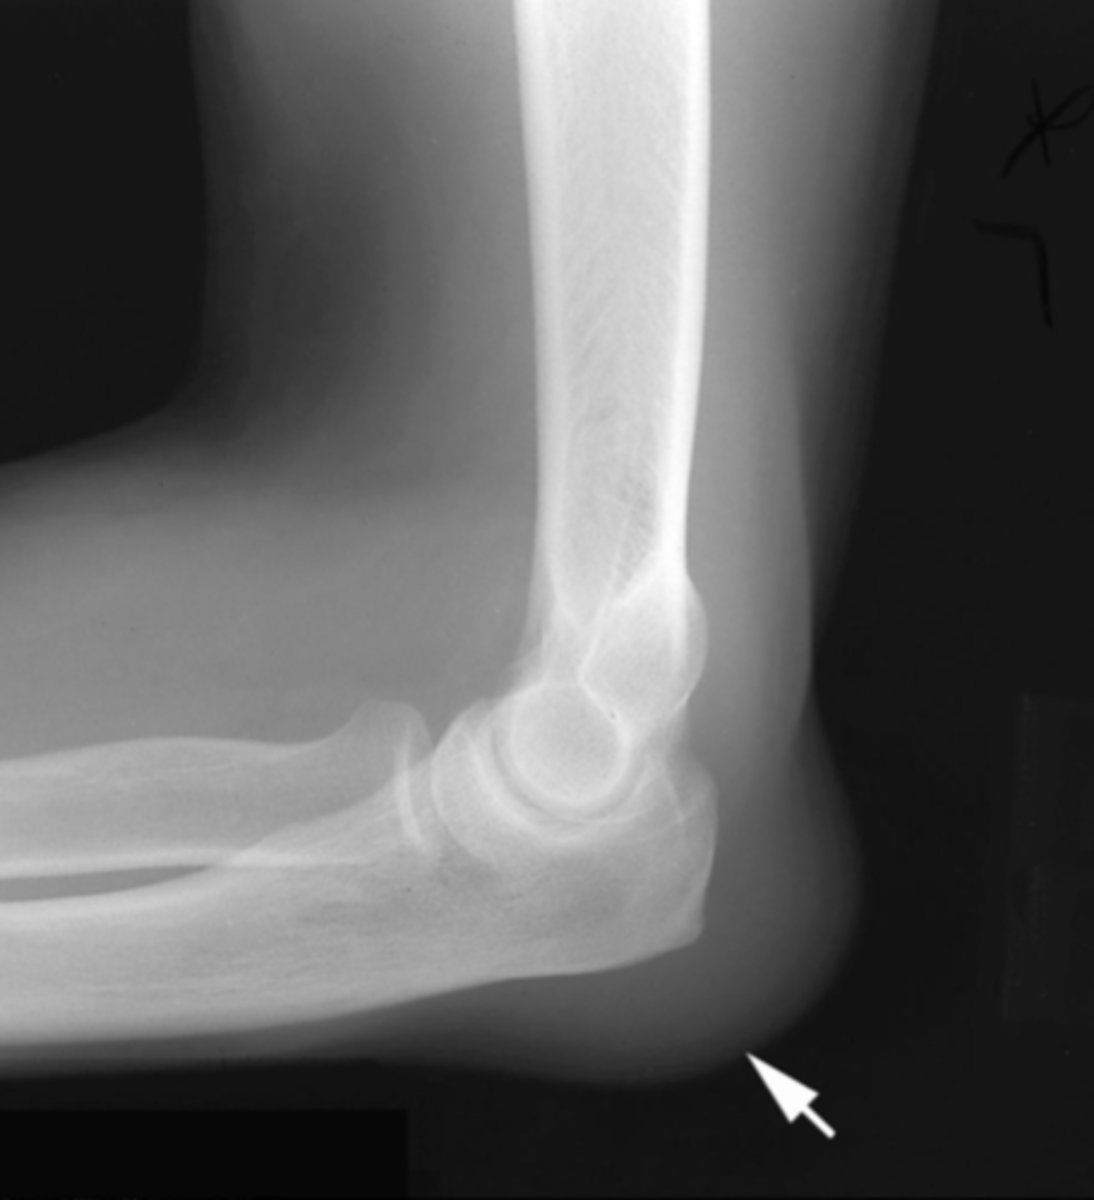

Lateral elbow

What view does this show?

positive fat pad sign

What is the issue?